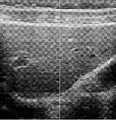

图7为一个实施例中弹性测量的超声成像系统实际使用过程中肝脏的二维超声图像;Fig. 7 is a two-dimensional ultrasound image of the liver during the actual use of the ultrasound imaging system for elasticity measurement in an embodiment;

图7示出了上述超声弹性成像系统实际使用过程中肝脏的二维超声图像,其中,白色线条表示待检测的肝脏区域,白色方框表示超声换能器阵列130聚焦位置。FIG. 7 shows a two-dimensional ultrasound image of the liver during the actual use of the above-mentioned ultrasound elastography system, where the white lines indicate the liver area to be detected, and the white squares indicate the focus position of the

图8示出了图7的白色线条对应位置的应变随时间的变化图像,其中,纵坐标表示肝脏深度,横坐标表示时间,黑色线条的斜率代表剪切波在肝组织中的传播速度。Fig. 8 shows the image of the strain over time at the position corresponding to the white line in Fig. 7, where the ordinate represents the depth of the liver, the abscissa represents time, and the slope of the black line represents the propagation speed of the shear wave in the liver tissue.